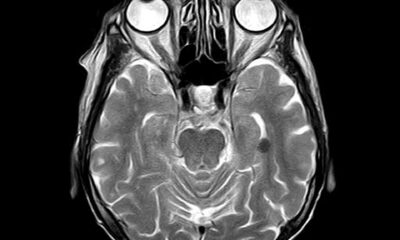

Un numero crescente di scienziati crede che una sorta di «pulsante del benessere» – un dispositivo che può essere impiantato nel cervello e innescare automaticamente sensazioni...

Gli scienziati di Stanford hanno sviluppato un impianto cerebrale che consente a un uomo con le mani paralizzate di «digitare» fino a 90 caratteri...

Scienziati in Corea del Sud hanno creato una nuova interfaccia neurale durevole in grado di misurare i segnali cerebrali direttamente all’interno del cervello stesso....